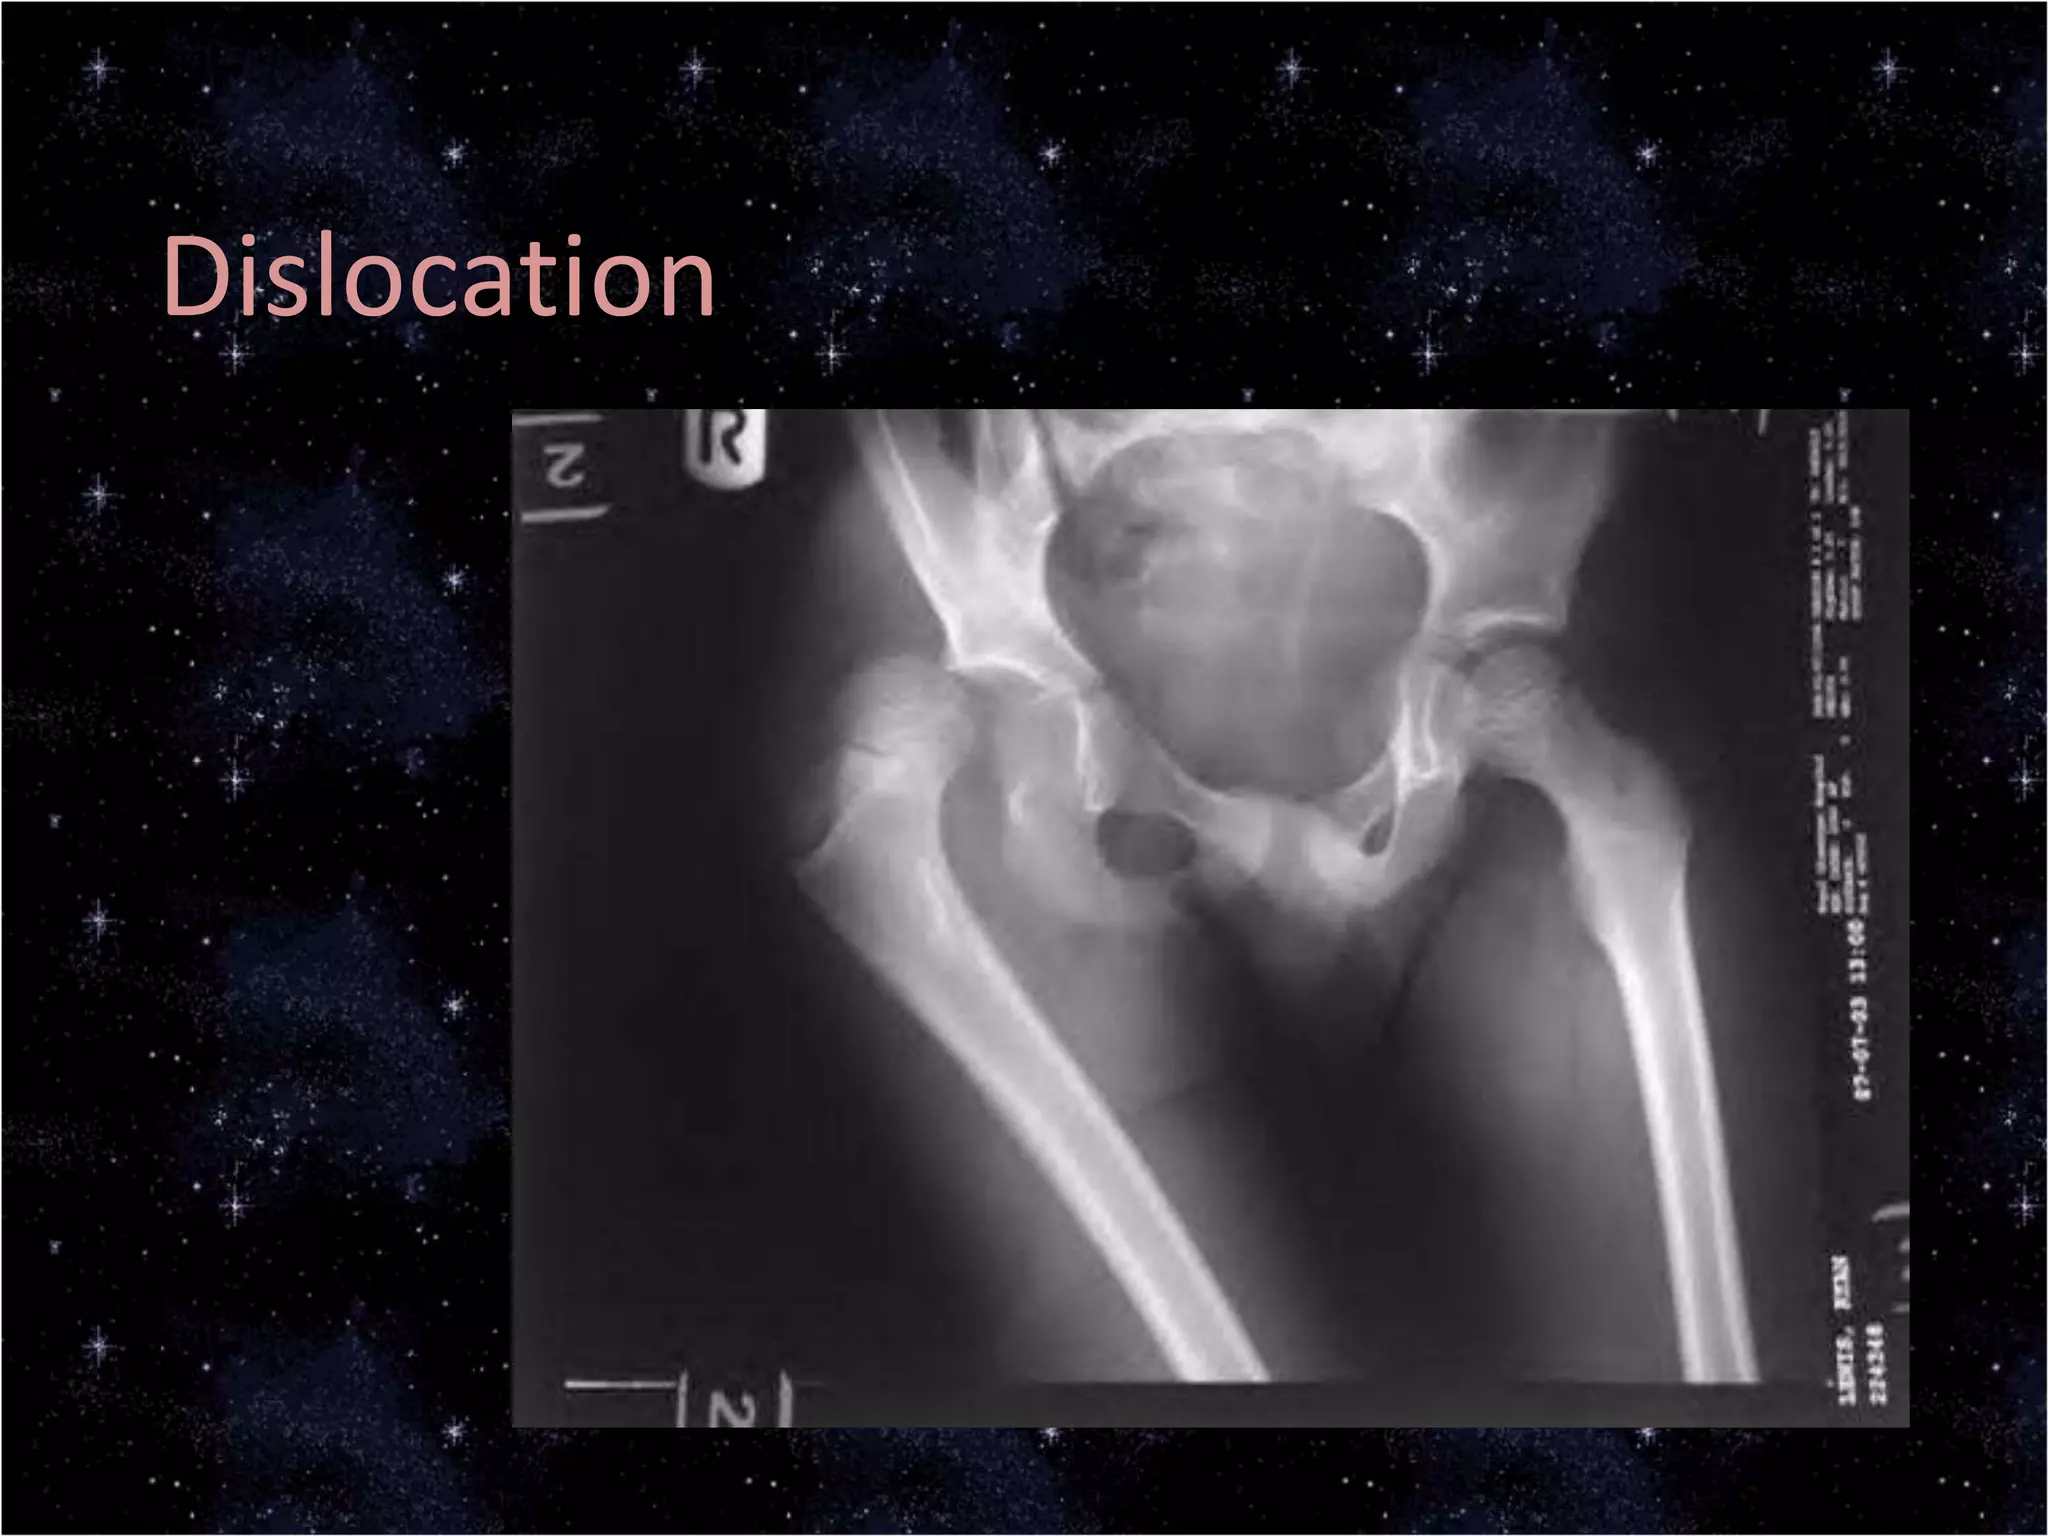

This document discusses trauma to the pelvis, hips, knees, ankles, and feet. It covers anatomy, imaging techniques, and types of fractures and dislocations that can occur in these areas. The types of fractures discussed include pelvic ring fractures, acetabular fractures, and fractures of the femur, tibia, fibula, and bones of the foot. Imaging views used include AP, inlet, and outlet views of the pelvis. Dislocations and fractures of the knee, ankle, and foot joints are also examined.